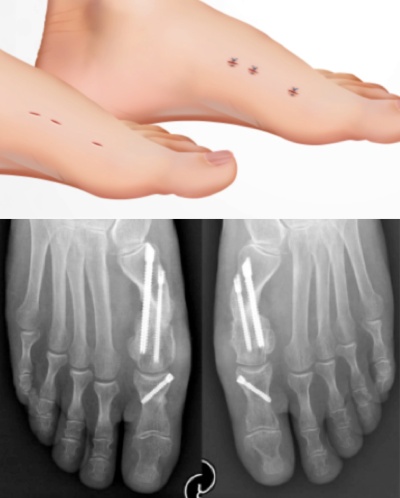

The bunion will be corrected by what is called an “osteotomy”. This means that the bone will be cut, shifted into the correct position and then fixed in place with screws. Most bunions will require two cuts and three screws. The cutting tool is not a saw, but a specialized cutting burr which uses high torque and low speed with irrigation. It is designed to cut bone and not tendon, nerves, or arteries; however, as in any surgery, there is always the potential for injury to these structures.

Because the procedure is done with x-ray guidance and is much more technically difficult, it typically takes longer than a traditional “open” technique. Average surgery times is 1-2 hours.